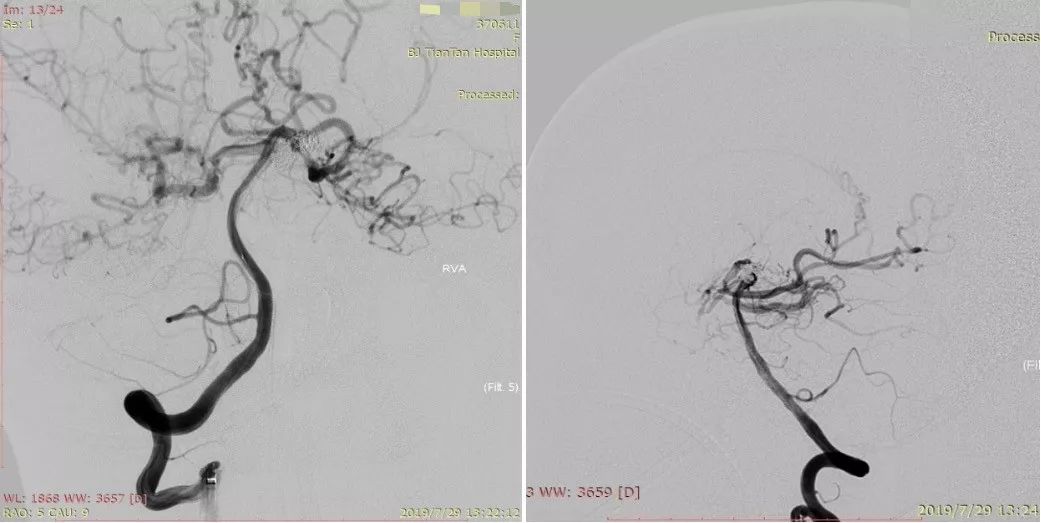

8年前动脉瘤治疗前后DSA(图2)

图2